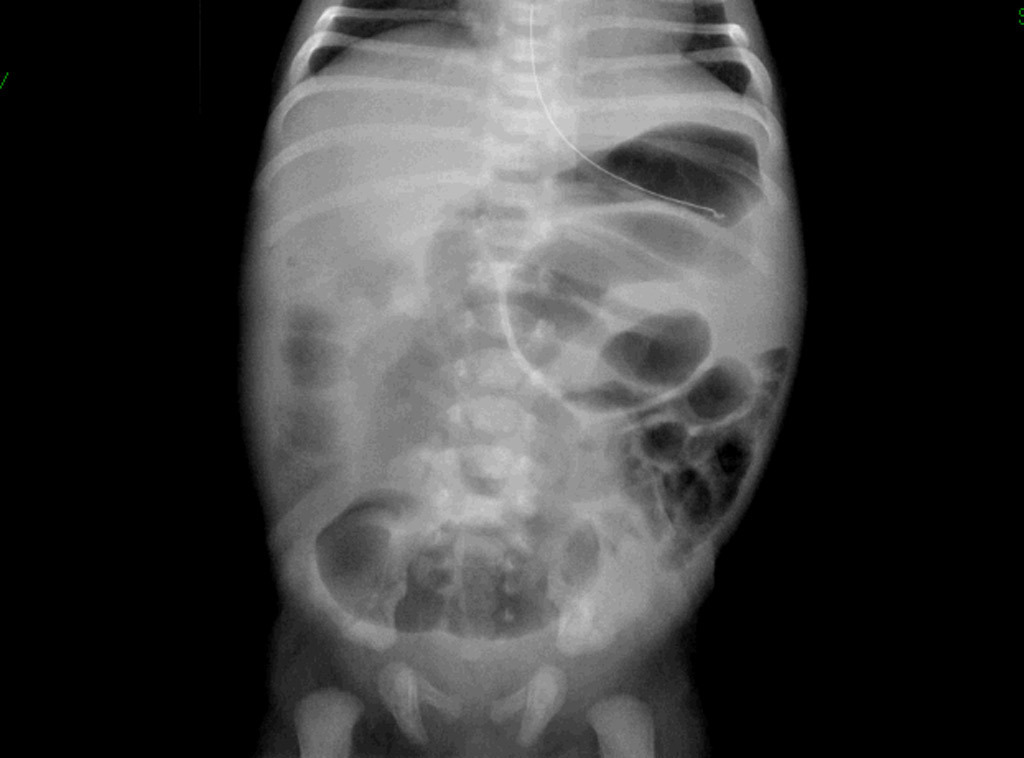

– ASP : double bulle ;